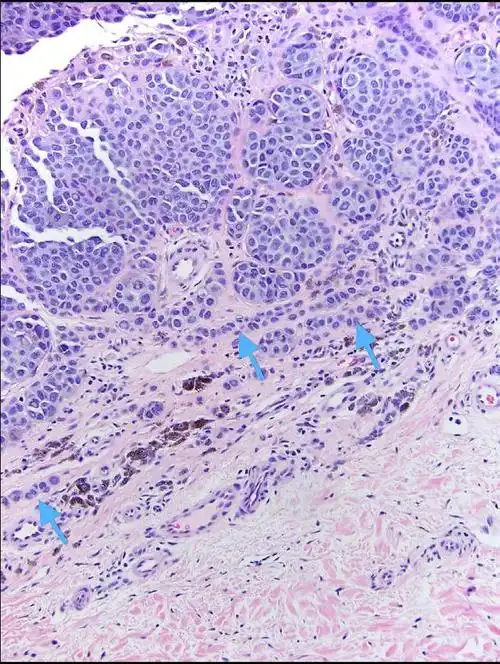

or 痣样黑素瘤? 低倍镜下有差别